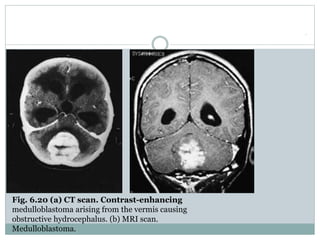

Fig. 6.20 (a) CT scan. Contrast-enhancing

medulloblastoma arising from the vermis causing

obstructive hydrocephalus. (b) MRI scan.

Medulloblastoma.